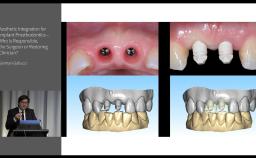

My ITI - German Gallucci

German Gallucci